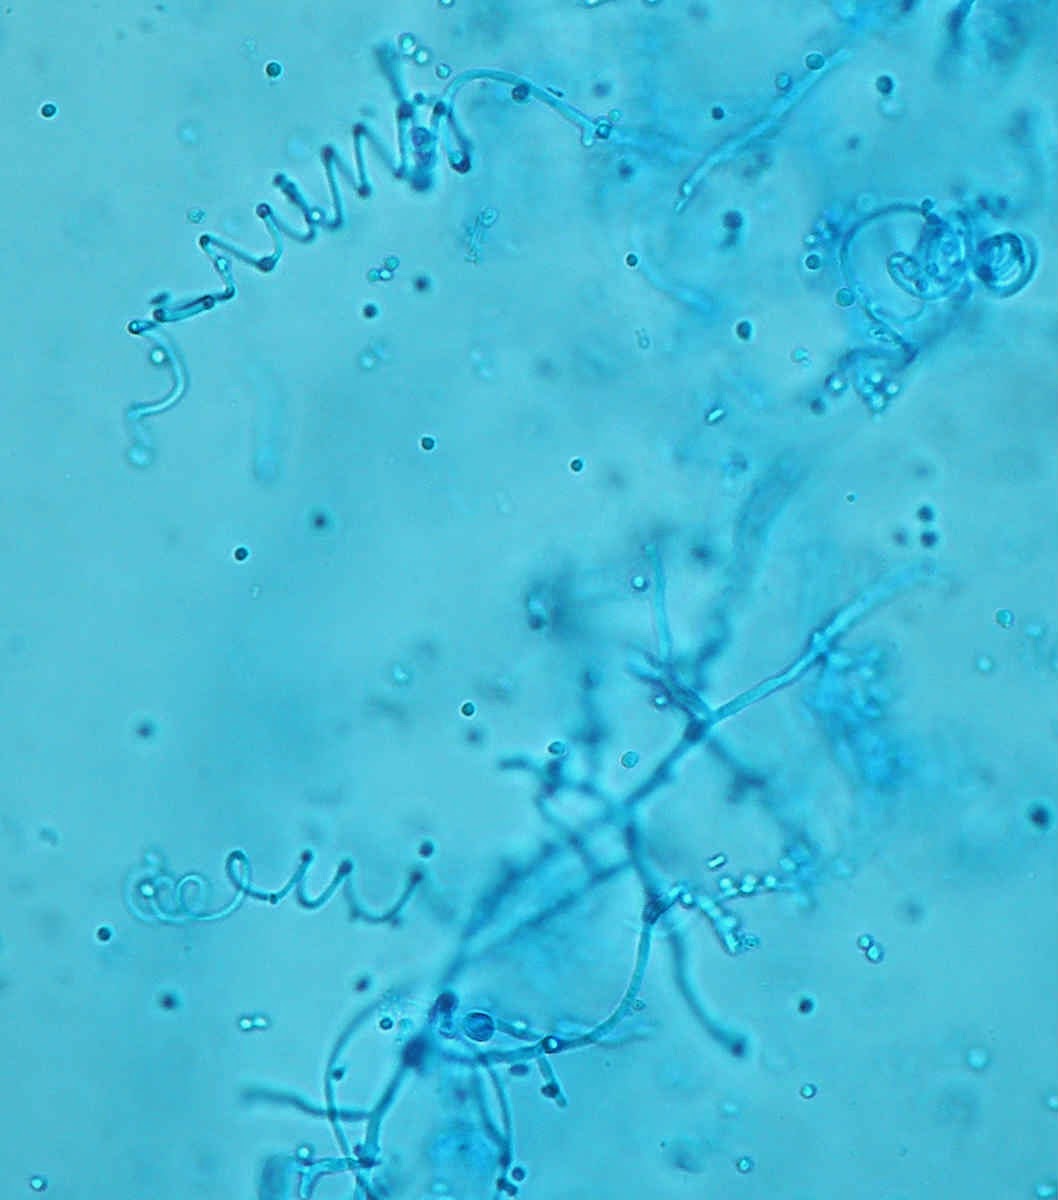

O exame microscópico confirma a identificação de T. mentagrophytes: hifas em espiral, microconideos esféricos.

Hifa em espiral.

Hifas espiraladas (azul lactofenol).